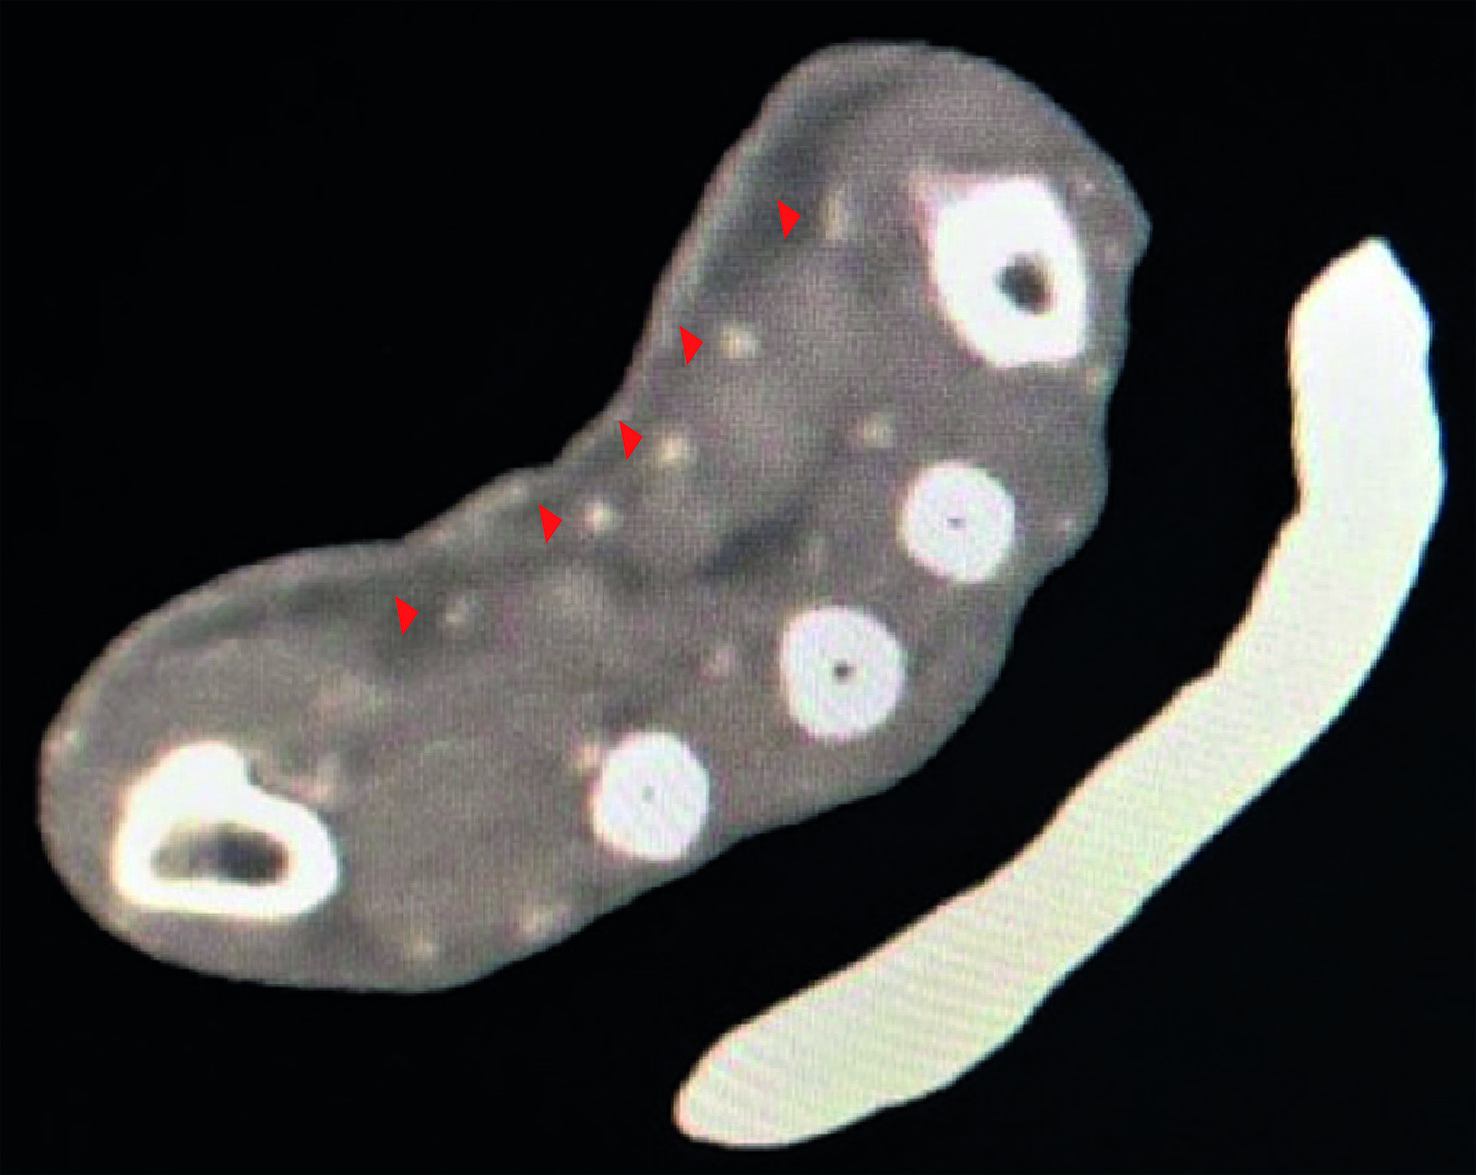

The imaging study showed a median artery originating as a continuation of the anterior interosseous artery (Figure 2) and ending in the palm with an incomplete superficial palmar arch (Figure 3). It was inferred that the preserved perfusion of the hand (Figure 4) without the need for anastomosis of the ulnar or the radial artery was secondary to the presence of the anatomical variant diagnosed in the scan (Figure 5). There was no adverse reaction to the contrast.

Figure 3 33-year-old male. A complete section of radial and ulnar arteries. The red arrow indicates the incomplete superficial palmar arch by the median artery. Angiotomography. Ioversol injection. 100 mL. 3 seconds.

Figure 4 33-year-old male. A complete section of radial and ulnar arteries. Red arrows are indicating the adequate perfusion of the hand. Angiotomography. Ioversol injection. 100 mL. 3 seconds.

Figure 5 33-year-old male. A complete section of radial and ulnar arteries. The red arrow indicates the median artery at the carpal level. The diameter of the persistent median artery at this level was 2.5 mm. Angiotomography. Ioversol injection. 100 mL. 3 seconds.

According to Eid, et al. classification, the patient had an incomplete superficial arch (Figure 4), type D pattern, in which the PMA does not anastomose with the radial or ulnar arteries. The PMA has been reported in a diameter ranging from 0.8 to 2.7 mm 9. The diameter of the PMA in the present report was 2.5 mm, which is in a high range compared to the literature. This finding could be explained that the radial and ulnar arteries were injured, and thus the PMA was dilated to be able to assume the perfusion of the hand.